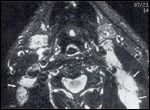

FIGURE 14

Lymph Node Necrosis

A heterogeneous appearance, enhancement (Figure 13), and/or frank central necrosis (Figure 14) strongly suggest the presence of metastatic tumor in the appropriate clinical context. (Infectious lymphadenitis may have the same appearance, however.) Even small lymph nodes (£ 5 mm) with a necrotic center are abnormal. These are often not clinically palpable, and their identification on imaging studies may alter the clinical stage of the tumor.

FIGURE 15

Abnormal Number of Lymph Nodes

It is important not to mistake the normal hilar fat in a node for central necrosis. This is only an issue on CT, as fat and necrosis have different signals on MRI.

Normal lymph nodes are oval, whereas round nodes often contain tumor. It is important to make sure that the scan is oriented along the long axis of the node before identifying a node as round. An increased number of nodes may also be abnormal (Figure 15).

Imaging studies are especially important for detecting clinically nonpalpable nodes.[17] These are not just small nodes. Retropharyngeal lymph nodes (nodes of Rouviere) are difficult or impossible to appreciate clinically but are easily identified on imaging studies (Figure 14). This important information may alter surgical planning or treatment options.